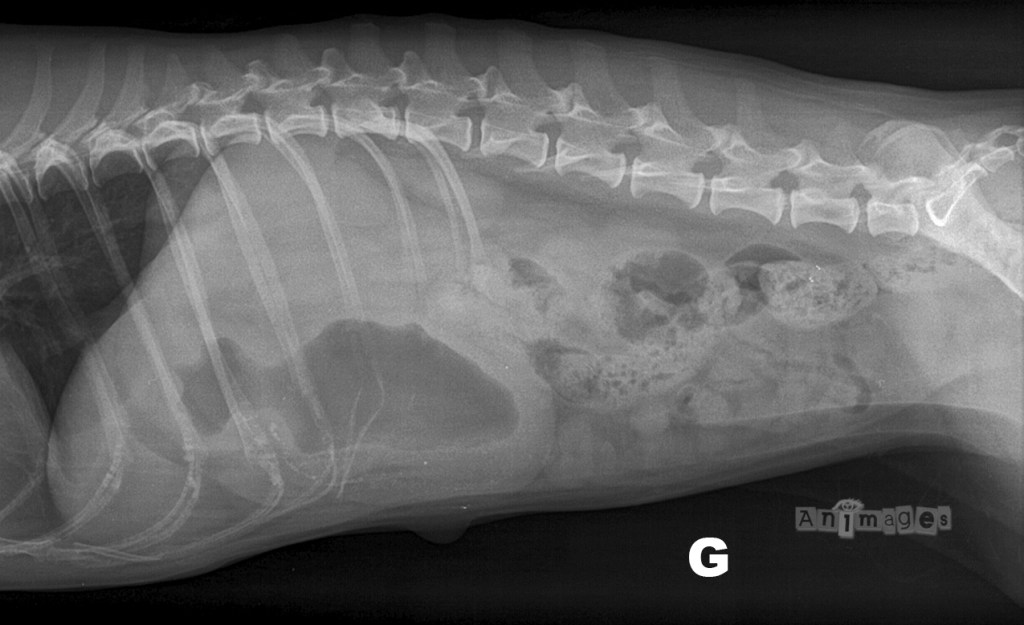

Latérale gauche